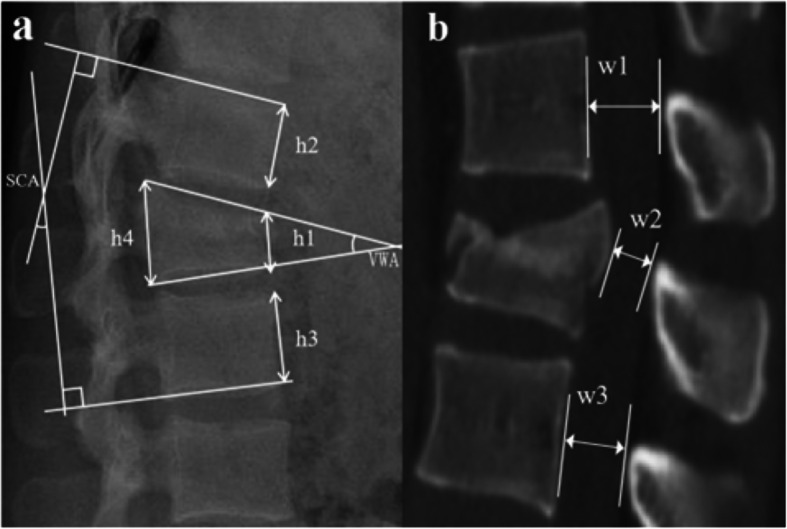

Clinical efficacy and radiological outcomes of a novel screw placement technique for the treatment of traumatic thoracolumbar vertebral fractures under navigation guidance.